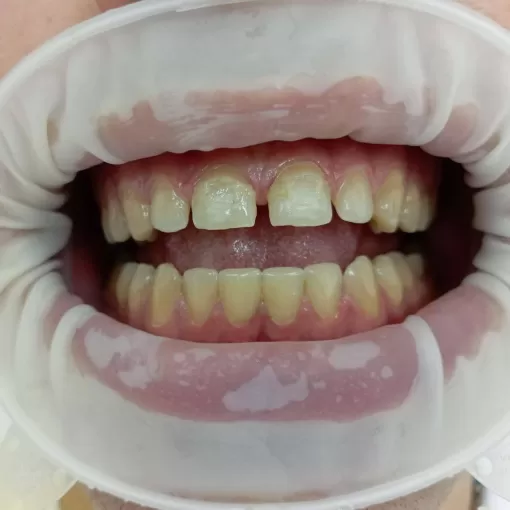

Совместная работа с ортодонтом, после брекет-системы эстетическая реставрация, устранение трем и диастем

Реставрация 21, 11